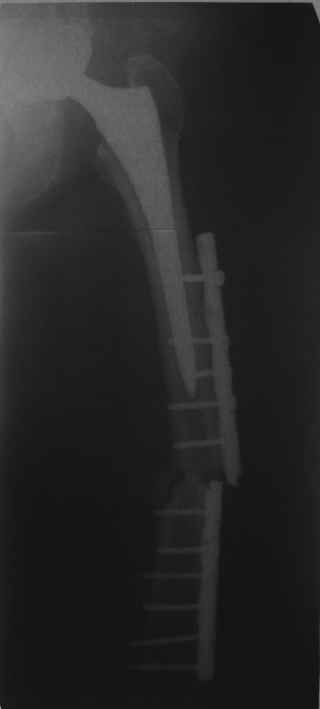

Сейчас опорную нагрузку на бедро берет на себя система от бедренного компонента эндопротеза до проксимального винта в интрамедуллярном гвозде. Свидетельство тому - реакция кортикала утолщением вокруг того самого винта. Таким образом вся кость от верхушки б.вертела до проксимального винта не испытывает физиологической осевой нагрузки. Результатом этого могут стать следующие последствия друг друга не исключающие: 1) все будет хорошо до перелома опорной системы по винту(ам) или в месте соединения штифта с ножкой или еще где-либо, 2) исключенная из-под нагрузки кость будет терять в количестве и качестве, что не очень (или очень не) хорошо для возможных будущих ревизий (тьфу-тьфу!!!).

Хотел бы обратить Ваше внимание, что реакция кортикала наблюдается только вокруг проксимального винта, дистальный винт не испытывает подобной нагрузки. Отсюда еще одна умозрительная авантюра - выкрутить только проксимальный винт. Изменения кости вокруг дистального винта тоже могут дать ответ на счет интеграции ножки, также как и появляется возможность сломать его. Страховаться (затратнее, но надежнее) или нет(легче, но не безопасно) динамическим винтом - на Ваш выбор.

О качестве сращения перелома тоже сказать трудно. Выраженной мозоли нет. В боковой проекции отломки накладываются друг на друга. В прямой проекции зона перелома в наружной части закрылась не полностью. Возможно причина тому - недогрузка кости.

Это сплошной титановый стержень. На дистальном конце отверстия под кондуктор. На другом - канал под ножку глубиной 60 мм, стенки толщиной 2,5-3 мм. И там же продольный пропил, чтобы канал мог адаптироваться к ножке.